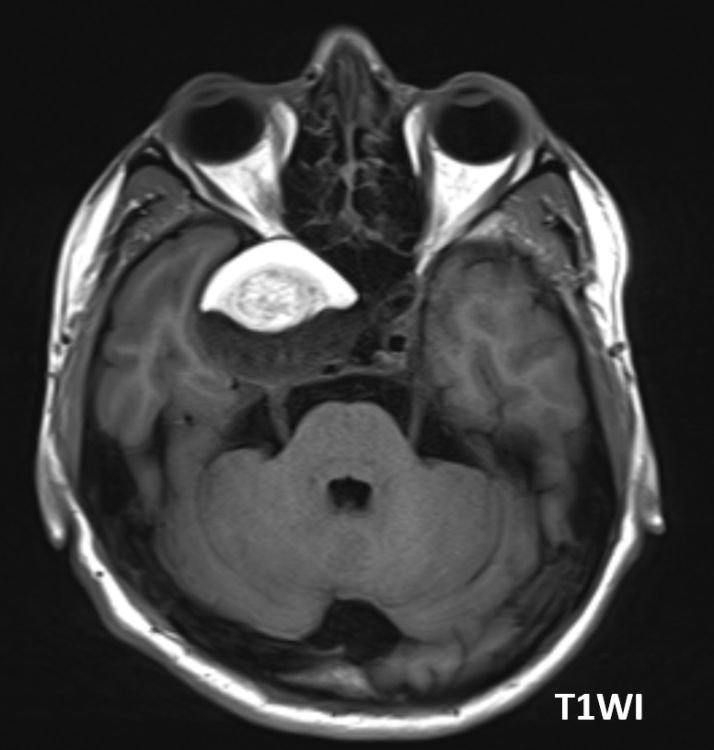

Intracranial HYPOtension, imaging findings and diagnostic approach Imaging and learning points in 🧵 🧠 #Neurology #neurosurgery #MedEd #radres #futureradres #neurorad American Society of Spine Radiology (ASSR)